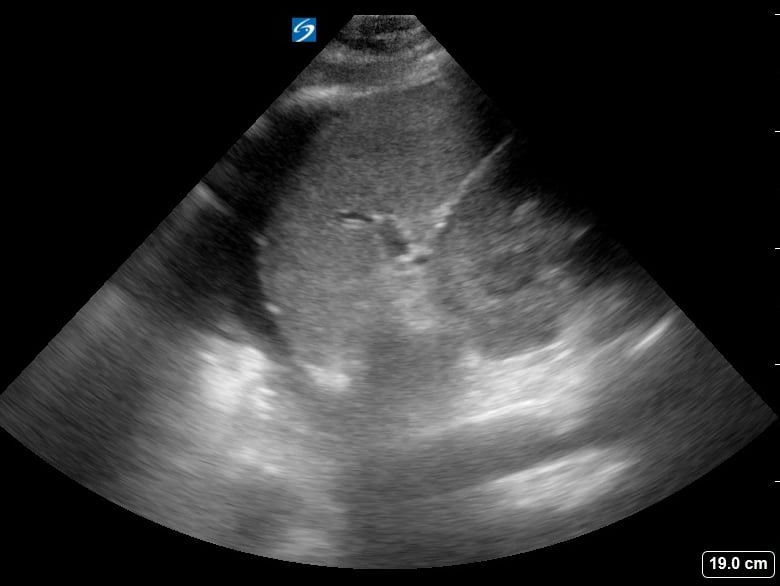

The “spine sign” in lung ultrasound refers to the abnormal visualization of the vertebral bodies above the diaphragm, a key indicator of pleural effusion. Normally, the air-filled lungs obscure the spine above the diaphragm. However, in the presence of fluid, sound waves can travel through the effusion, allowing the spine to be seen. This finding is crucial for diagnosing fluid accumulation in the thoracic cavity.

Recognizing the spine sign is essential for medical professionals using point-of-care ultrasound. Its presence confirms a significant pleural effusion, guiding further diagnostic and therapeutic interventions. This simple yet powerful ultrasound sign enhances rapid assessment in emergency and critical care settings, improving patient management.